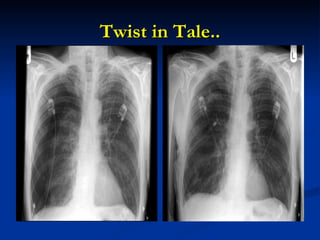

Twist in Tale..

CXR with recurrent right-sided pneumothorax, despite thoracostomy tube in place CT scan with giant bullae and anterior pneumothorax after insertion of a second thoracostomy tube

CXR with recurrentright-sided pneumothorax, despite thoracostomy tube in place CT scan with giant bullae and anterior pneumothorax after insertion of a second thoracostomy tube